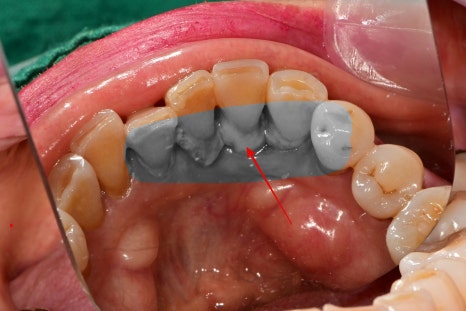

아래 앞니 쪽 안쪽으로 치석이 많이 쌓여있었는데

주변 잇몸이 많이 부어있고, 치아에 동요도가 생긴 상태였습니다.

다행히염증은 많이 진행된 상태는 아니라

스케일링 후 잇몸치료를 진행하여 건강하게 회복되었습니다.

일반적으로 아래턱 앞니 안쪽은

침샘과 가깝고, 칫솔질의 각도가 용이하지 않기 때문에

치석이 잘 쌓이는 환경입니다.

사진과 같이 치석이 쌓이며

더 이상 치아가 지지를 못 받을 정도로 치주염이 진행된 상태입니다.

이 정도로는 잇몸치료를 하더라도 치아의 흔들림을 잡아줄 수 없기 때문에

해당 케이스는 발치를 진행했던 경우입니다.